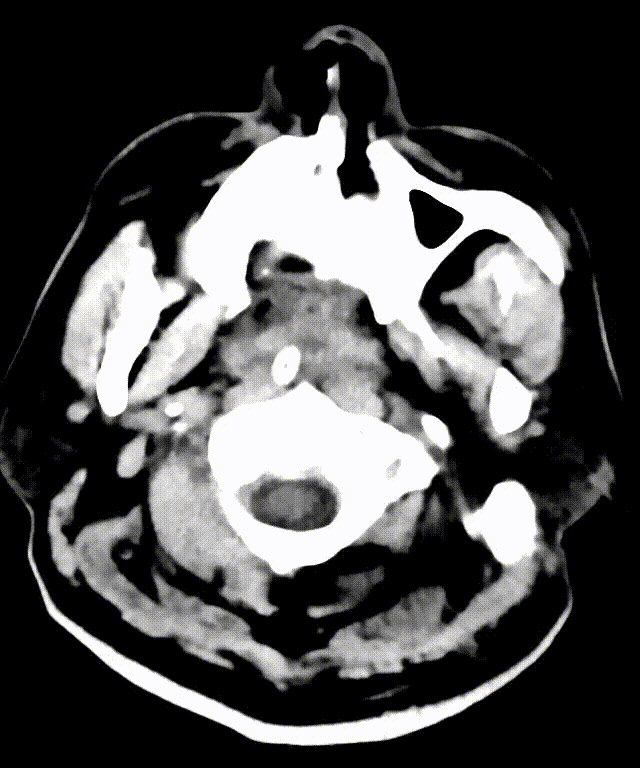

主动脉弓造影未见明显异常。

主动脉弓造影提示双侧椎动脉V4段闭塞。

左侧椎动脉造影提示椎动脉V4段闭塞。

主动脉弓造影:主动脉弓呈"Ⅰ"型弓,依次发出头臂干、左侧颈总动脉起及左侧锁骨下动脉,以上三支血管开口未见无明显狭窄、扩张及斑块形成,前向血流正常。

猪尾巴导管行全脑血管造影,可见双侧椎动脉V4段闭塞。

左侧椎动脉造影提示左侧椎动脉V4段闭塞;右侧锁骨下动脉造影提示右侧椎动脉纤细并V4段闭塞。